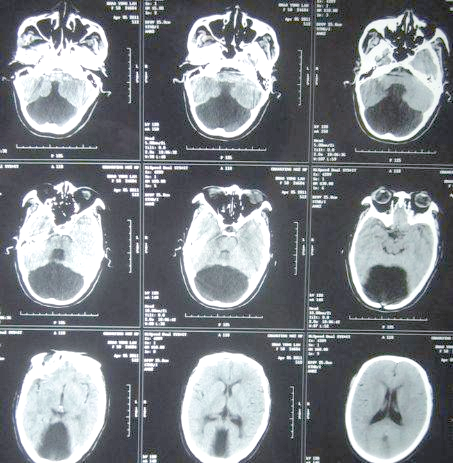

大枕大池是什么意思

大枕大池:常见解剖变异